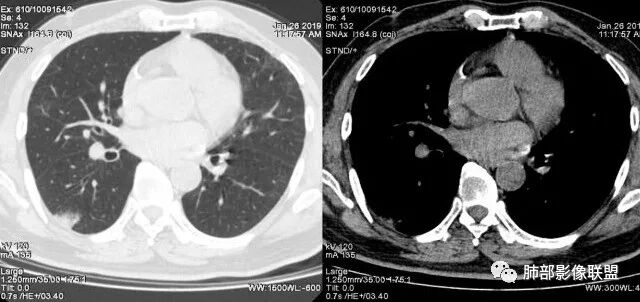

我觉得纵膈窗可以更好观察,纵窗看支气管很紊乱的感觉,鉴别,肺炎的支气管充气征,支气管走形还是很自然的

右肺下叶胸膜下大片状MGGO,其内结构紊乱,可见空泡征,病灶内近端支气管扩张,远端闭塞,形态不规则,边界部分清楚,部分似清非清,考虑粘液腺癌,鉴别淋巴瘤

该病灶主病灶位于胸膜下(肋膈角处),边缘膨隆改变,周围毛玻璃,边界清楚,病灶内支气管僵直,轻度扩张,小分支无,符合枯树枝改变,有多发小空泡(难与支气管区别),应该符合肺炎性肺癌,但无蜂窝,没有增强无法判断有无粘液、血管特点,如果周围显示的空泡是支气管,其已达到远端,这些有符合炎性特点,工作中,我会先抗炎膨后复查再定。

这是潘老师说的外向内吗?右下实变,蜂窝,GGO,支气管变形迂曲,局部膨胀感,肺炎性肺癌,粘液腺癌可能。常规先抗炎再复查。鉴别淋巴瘤,淋巴瘤支气管一般不变形,壁光整,病程长。

2.病灶示中央实变区,周围GGO,可见明显小叶间隔增厚,GGO边界清楚,应当考虑到恶性病变的可能性。肺炎因炎性水肿及渗出,影像上边界常模糊不清,注意早期粘液腺癌可出现似清非清的边界。粘液腺癌因粘液成份较多,密度一般偏低,纵隔窗病灶常会消隐或范围会明显缩小,这不同于炎性实变。

3.病灶内支气管走形略显僵直,侧支少(粘液阻塞),也符合肺腺癌的枯树枝征。而大叶性肺炎的支气管是管壁光整、通畅、自然,结核的支气管常常壁增厚,甚至狭窄后扩张;